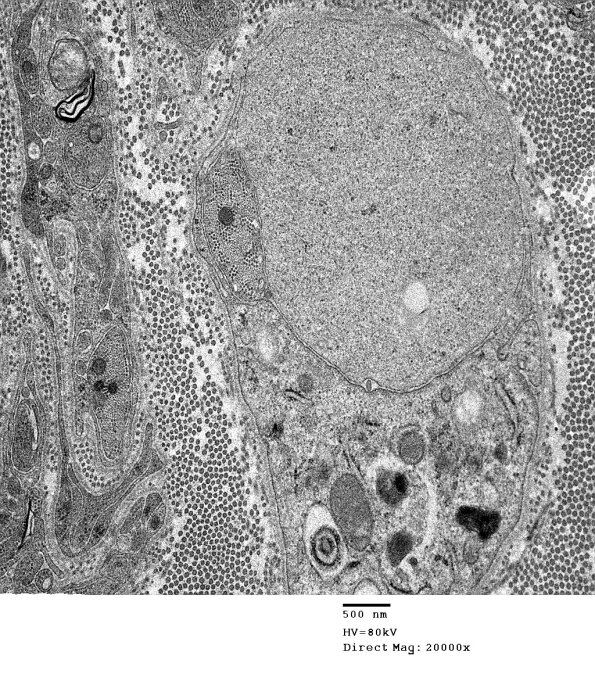

There were numerous examples of demyelinated axons in anticipation of remyelination. (electron micrograph) ---- Denouement: We think that this case represents fulminant GBS in which marked axonal degeneration dominants this histopathology and ultrastructure.